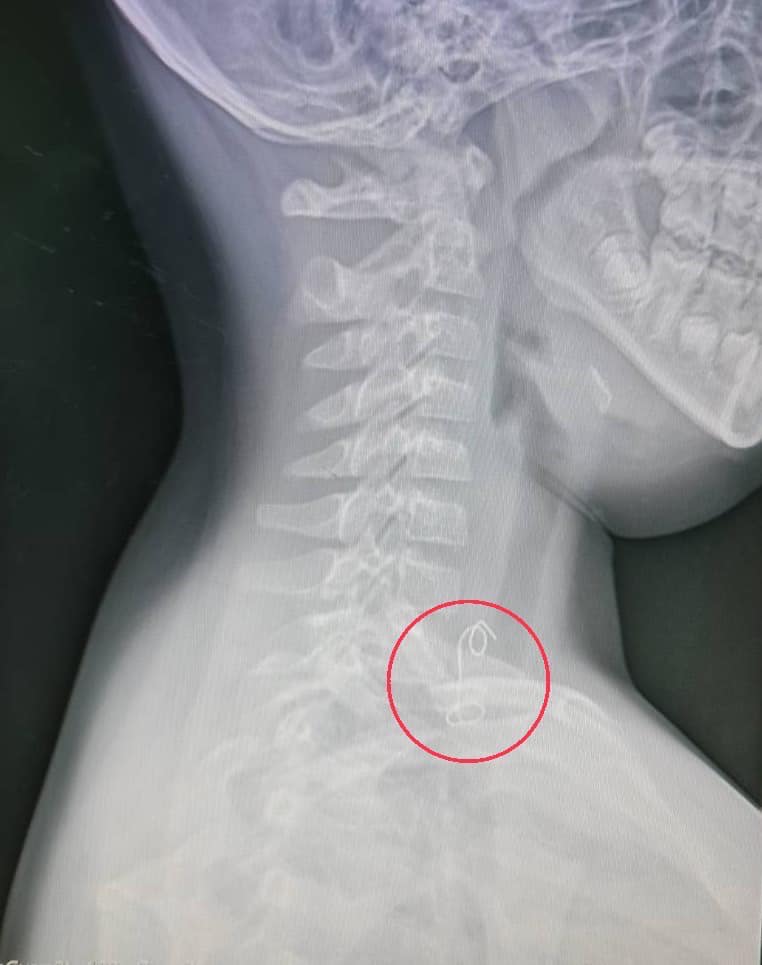

“เด็ก8ขวบ กินไก่ย่าง กลืนลวดผูกมัดไก่ย่างติดไปด้วย ติดค้างฝังในผนังหลอดอาหารส่วนบน ต้องผ่าตัดฉุกเฉิน

จึงสงสัยว่าอาจมีกระดูกไก่ติดคอ หาน้ำมาให้ดื่มตามไป แต่ยิ่งกลืนยิ่งปวด ร้องไห้ระงม รีบพาส่งโรงพยาบาล แพทย์ห้องฉุกเฉินส่งเอกซเรย์ เห็นเป็นวัตถุคล้ายขดลวดติดอยู่บริเวณส่วนต้นหลอดอาหาร ปรึกษาแพทย์ผู้เชี่ยวชาญด้านหู คอ จมูก เปิดห้องผ่าตัดด่วน ต้องดมยาสลบวิธีพิเศษใส่ท่อช่วยหายใจทางจมูกเพื่อป้องกันไม่ให้สำลักระหว่างผ่าตัด ใช้เครื่องมือส่องกล้องคีบเอาสิ่งแปลกปลอมออกมาได้

สิ่งที่เห็นนอกจากเศษปีกไก่ย่างที่ยังติดค้าง รวมไปถึงลวดมัดไก่ย่าง ยาวประมาณ 8 เซนติเมตรออกมาด้วยได้สำเร็จ ผู้ป่วยพักฟื้นในโรงพยาบาลฉีดยาต้านเชื้อ 3 วัน ให้กลับบ้านได้ อย่างปลอดภัย เตือนภัยใกล้ตัว ให้บุตรหลานกินอาหารไก่ย่างมัดลวดต้องระวังให้ดี”